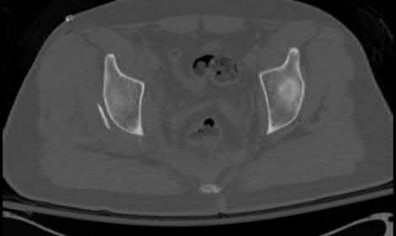

A poly-trauma patient presents hemodynamically unstable with an anteroposterior compression (APC-III) pelvic ring injury. A circumferential pelvic binder is requested to reduce pelvic volume and control hemorrhage. To be anatomically effective, the binder must be centered precisely over which of the following landmarks?

Explanation

For optimal mechanical advantage and effective reduction of an 'open book' pelvic fracture (APC type), a pelvic binder must be applied directly over the greater trochanters of the femurs. Applying it higher, such as over the iliac crests, is a common error that fails to adequately close the pelvic ring and can paradoxically open the true pelvis.